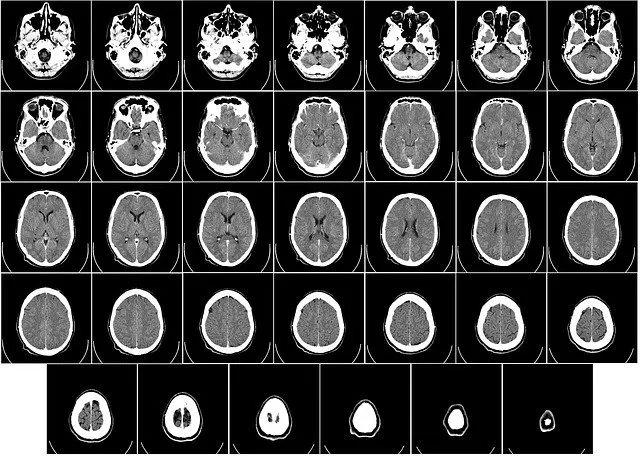

Jakie obrazy uzyskuje się podczas badania TK?

Badanie tomografii komputerowej dostarcza różnorodnych obrazów, które mogą być zarówno dwu-, jak i trójwymiarowe. Obrazy te charakteryzują się wysoką jakością i precyzją, co pozwala na dokładną ocenę stanu zdrowia pacjenta. Tomografia komputerowa jest szczególnie przydatna w identyfikacji zmian patologicznych, takich jak guzy, urazy czy inne nieprawidłowości w strukturze ciała.

Tomografia komputerowa (TK) odgrywa kluczową rolę w medycynie ratunkowej, gdzie szybka i dokładna diagnoza jest niezbędna. W przypadku urazów głowy, TK pozwala na błyskawiczne wykrycie krwotoków, złamań czaszki oraz obrzęków mózgu. Ponadto, w sytuacjach nagłych, takich jak wypadki samochodowe, tomografia komputerowa umożliwia ocenę stanu narządów wewnętrznych, takich jak śledziona, wątroba czy nerki, co jest kluczowe dla podjęcia szybkich decyzji o dalszym leczeniu.

W przypadku pacjentów z objawami udaru mózgu, TK jest niezastąpiona w określeniu, czy udar jest niedokrwienny, czy krwotoczny. Dzięki temu lekarze mogą szybko wdrożyć odpowiednie leczenie. Dodatkowo, tomografia komputerowa jest często wykorzystywana do oceny obrażeń klatki piersiowej, takich jak złamania żeber czy uszkodzenia płuc, co może być decydujące w sytuacjach zagrażających życiu.